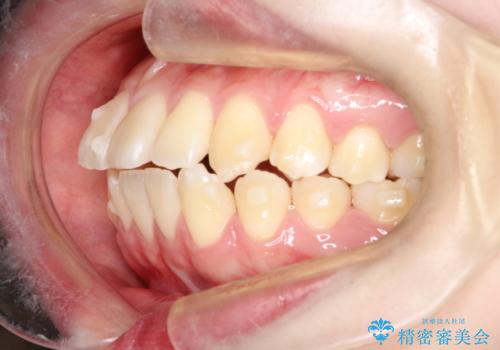

【インビザライン】歯を抜かずにできるだけ前歯を下げたい

- 前歯の前突を主訴に来院されました。

インビザライン を用いて、歯並びの改善を行うことができました。